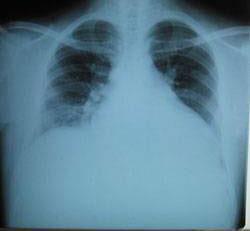

摘要:關(guān)于擴張性心肌病的最新治療,小巷深處的隱藏寶藏正逐漸為人們所發(fā)現(xiàn)。通過先進的醫(yī)療技術(shù)和方法,擴張性心肌病的治療取得了新的進展。這些治療方法旨在改善心臟功能,提高患者生活質(zhì)量。小巷深處的醫(yī)療機構(gòu)或?qū)<铱赡茈[藏著寶貴的治療經(jīng)驗和方法,為尋求最佳治療方案的病患帶來希望。更多詳細信息需要進一步探索和研究。

擴張性心肌病是一種嚴重的心臟疾病,但“心之港灣”為你帶來希望,這里的專家團隊一直在深入研究擴張性心肌病的最新治療方法,并深知每位患者都渴望得到最佳的治療和關(guān)懷,他們努力不懈,為患者帶來生機和新生。